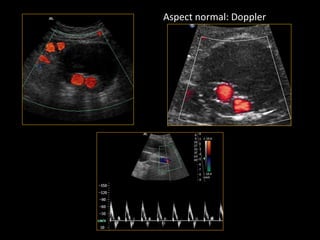

Aspect normal: Doppler

• Perméabilité de la prothèse (Doppler)